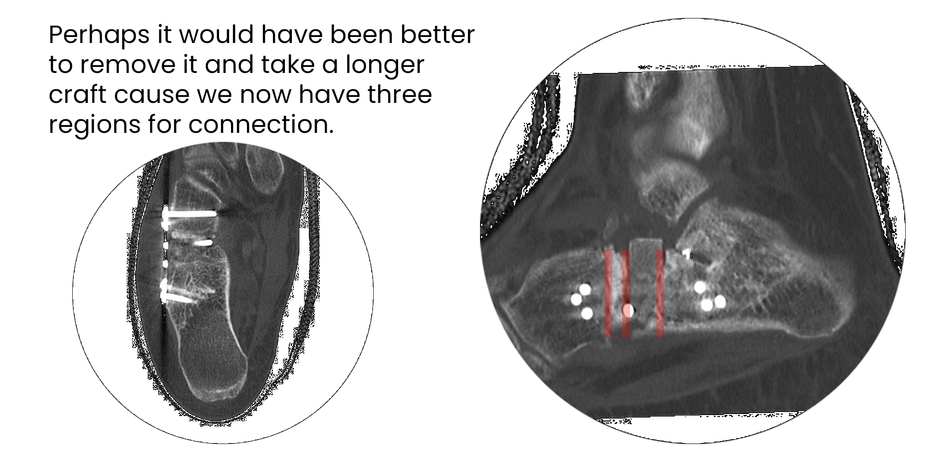

case 17LC, 29 years old, female, fall from horse

with the foot caught in the stirrup

"atypical fracture", surgery 19 hours after trauma